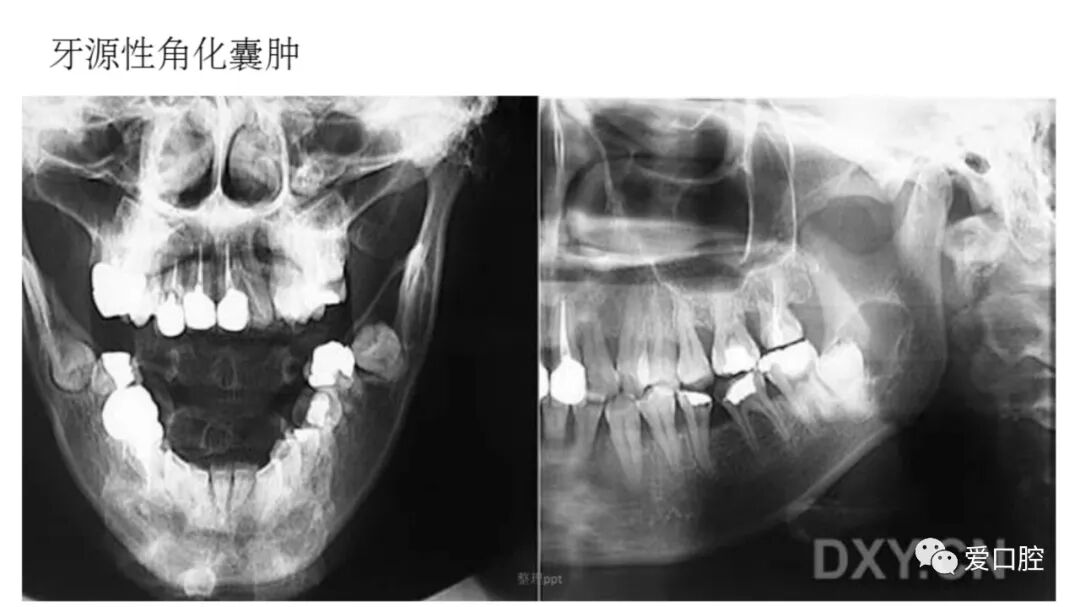

口腔小技巧 | 口腔科常见的病例影像!